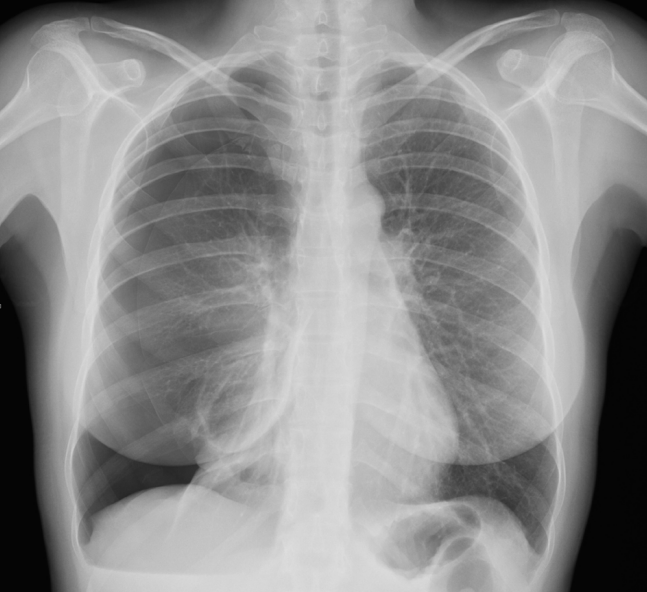

Catamenial Pneumothorax: A Challenging Diagnosis

Catamenial pneumothorax is the most frequent manifestation of thoracic endometriosis: this article is about a case in which the diagnosis was formulater only when a temporal connection with menstrual bleeding was noticed and when implementation of a specific medical treatment was able to prevent further recurrences of the desease.